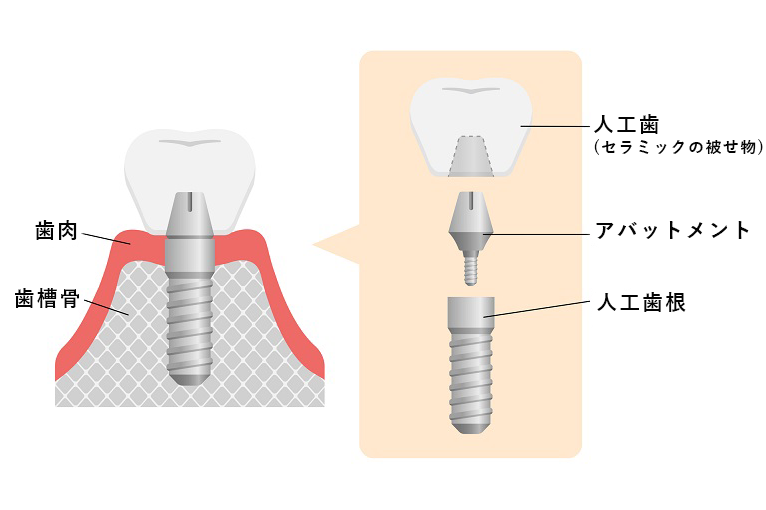

インプラントは、人工歯根、アバットメント、人工歯(セラミックの被せ物)の3パーツで構成されます。

一次手術では、顎の骨に人工歯根を埋め込みます。

一次手術では、顎の骨に人工歯根を埋め込みます。